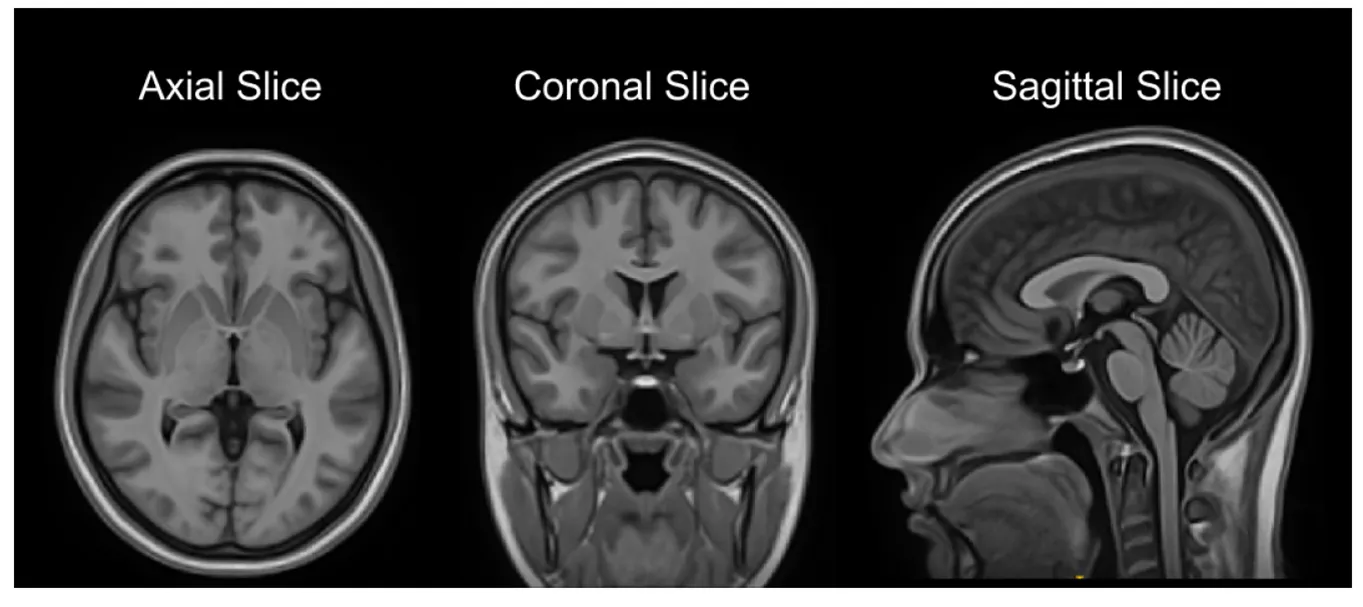

"The Montreal Neurological Institute (MNI) and the International Consortium for Brain Mapping (ICBM) created the first digital human brain atlas using the brain MRI volume of 305 young Caucasian subjects in the year 1993 . . .However, these brain atlases do not account for differences across phenotypic groups (e.g., age, gender, race, or disease conditions) as they are created using brain MRI of mostly Caucasian population. Of late, many studies have shown that there is a morphological difference across phenotypes. Specifically, this difference relative to the Caucasians has been reported for the East Asian populations as well as for the African‑American ones," says the published study titled 'Construction of Indian human brain atlas' in the journal Neurology India.

"With the revelations on the Indian brains, the differences in the MRI scans that can emerge by the comparisons (since Indian brains are smaller than Caucasian) can look alarming and lead to misdiagnosis," said Professor Jayanthi Sivaswamy, speaking to The Hindu Business Line.

“MRI images taken are compared with the pre-loaded MNI template to arrive at a diagnosis, and are likely to lead to a misdiagnosis. In practise, many doctors may use their experience to take a judgement call. The atlas will provide a more quantitative way and remove this dependency on experience,” says Professor Sivaswamy, speaking to The Better India (TBI).